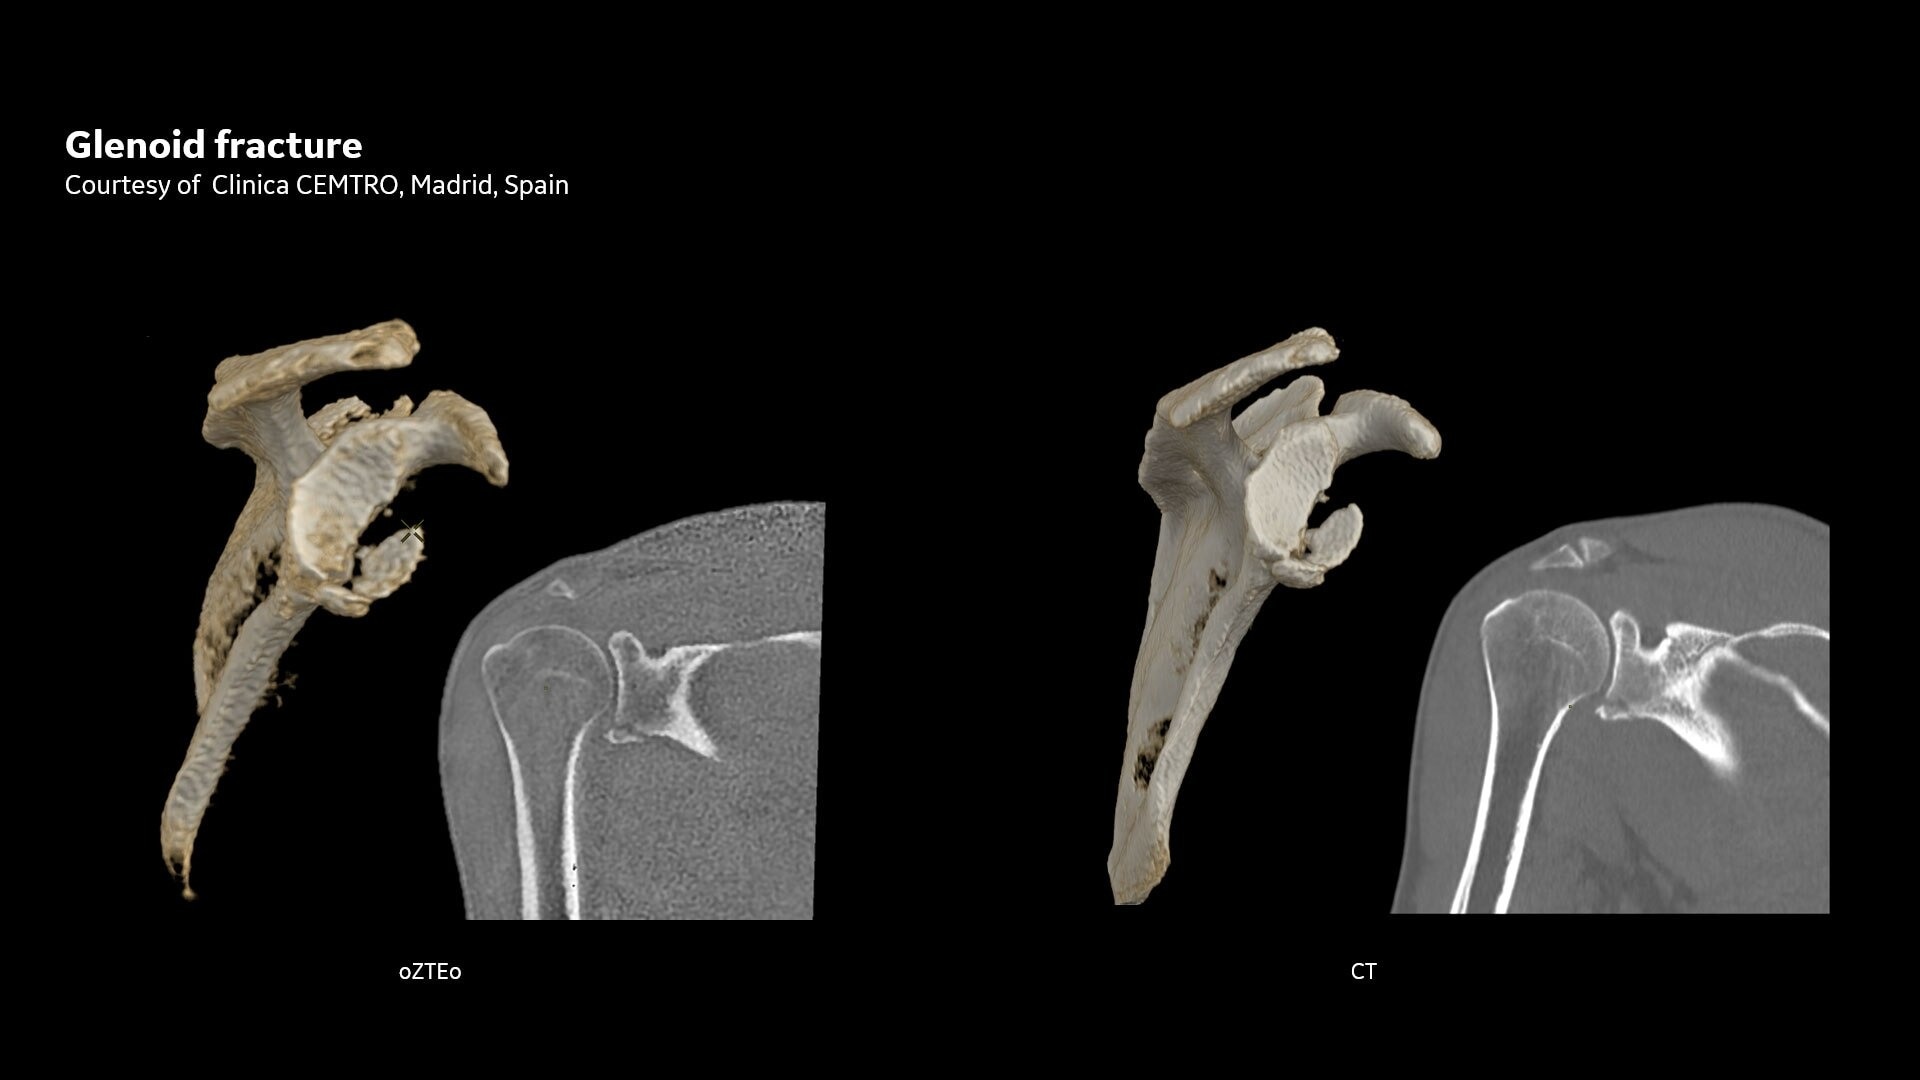

One-stop Orthopedic Shop

Provides cortical bone information co-registered with the soft tissue series

CT-like Image Contrast